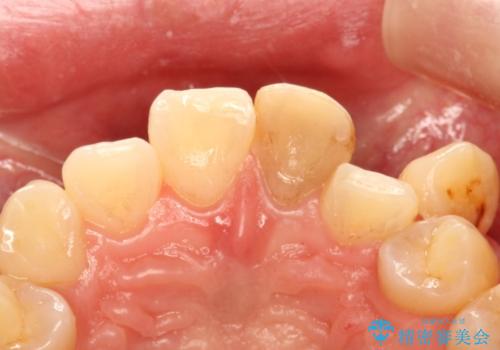

- 他院で前歯の変色をダイレクトボンディングにて修復治療しておりましたが、審美障害を主訴に来院されました。

根管治療後、オールセラミックにて治療を行っております。

ダイレクトボンディングはセラミックに比べ経年劣化しやすい材料です。

今回はオールセラミッククラウンによる治療を行いより審美的な修復ができました。